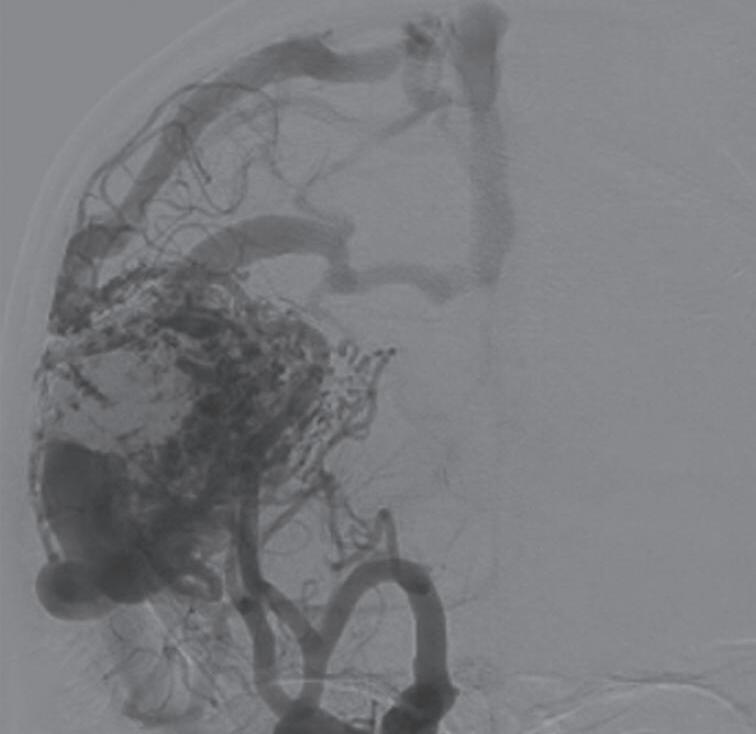

Com relação ao fluxo no interior do nidus, alguns autores classificam-nas em alto fluxo (Fig. 1-8) e baixo fluxo (Fig. 1-9). São consideradas de alto fluxo aquelas em que a opacificação após injeção de contraste ocorre apenas na malformação, em contrapartida, nas de baixo fluxo, ocorre opacificação da MAV e de outras artérias normais do mesmo território vascular. Exemplificando as lesões de alto fluxo temos as malformações arteriais, as malformações arteriovenosas e as fístulas arteriovenosas, enquanto as lesões de baixo fluxo são representadas pelas malformações venosas, linfáticas e capilares.25

A arteriografia cerebral digital com subtração é considerada o exame padrão-ouro para avaliação das MAV, possui excelente resolução espacial e temporal, o que é necessário para avaliar o tamanho do nidus, a presença de estenose de artéria nutridora, da veia de drenagem, avaliar a presença de aneurismas arteriais e venosos e o fluxo da malformação. Rotineiramente ela deve ser realizada pelo cateterismo dos seis vasos (carótidas internas, externas e artérias vertebrais) e a descrição do exame necessita conter a localização anatômica da malformação, além dos seguintes achados (Figs. 1-24 e 1-25):

Artérias:

• Tipo e número de aferentes arteriais.

• Presença de aneurismas associados (no vaso nutridor ou intranidal).

• Colaterais em territórios vasculares adjacentes (podem ser mal interpretadas como nidus).

Shunt:

• Nidus compacto ou difuso.

• Presença de fístulas de baixo ou alto fluxo.

Veias:

• Número de veias de drenagem.

• Localização superficial ou profunda.

• Presença de estenose ou ectasia.

• Grau de congestão venosa.39